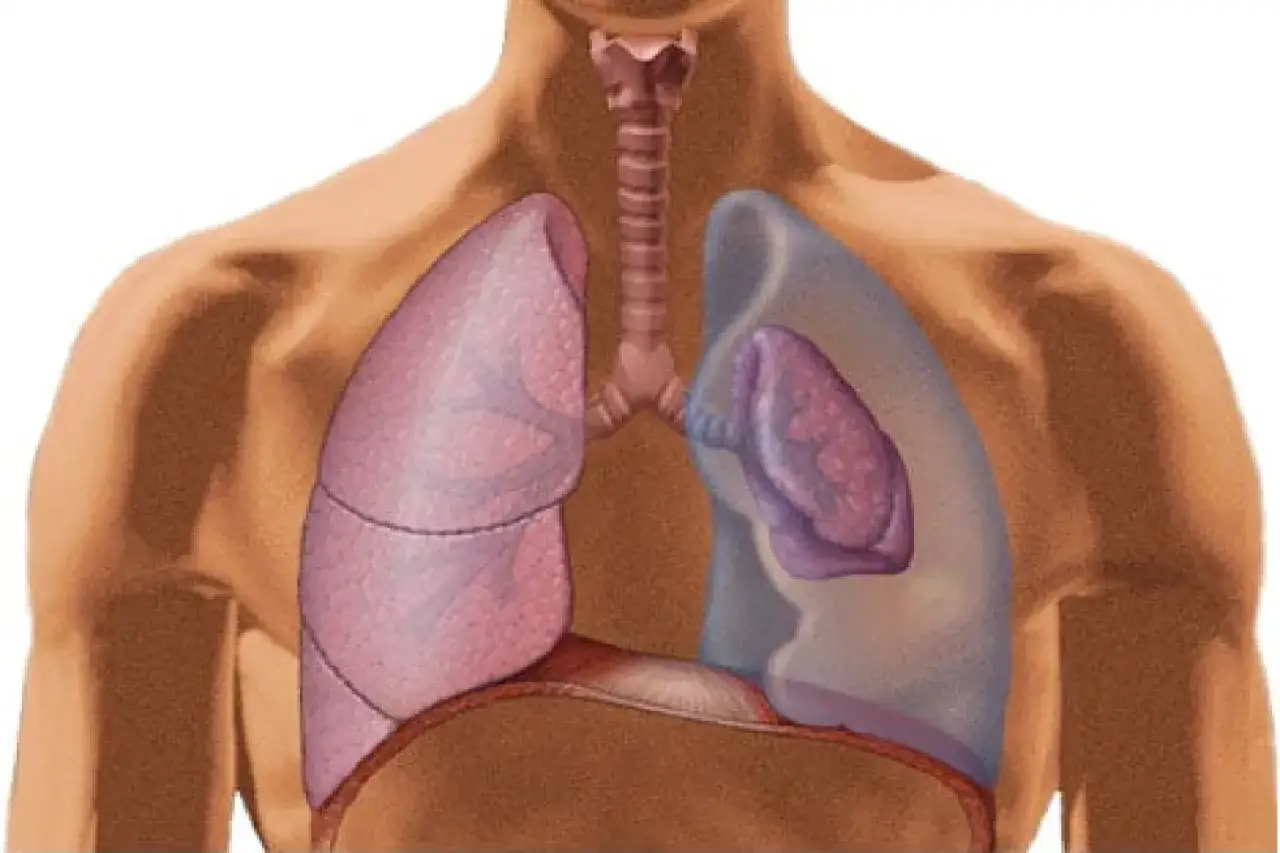

Odma płucna, znana również jako odma opłucnowa, to stan, w którym powietrze gromadzi się w jamie opłucnej. Jama opłucnowa to niewielka przestrzeń między dwiema błonami – opłucną płucną (pokrywającą płuco) i opłucną ścienną (wyściełającą wewnętrzną stronę klatki piersiowej). W warunkach fizjologicznych w tej przestrzeni panuje ujemne ciśnienie, które pozwala płucom swobodnie rozprężać się i kurczyć podczas oddychania.

Kiedy do jamy opłucnej dostaje się powietrze, ciśnienie w niej wzrasta. To z kolei prowadzi do ucisku na płuco, co utrudnia jego prawidłowe funkcjonowanie. Płuco staje się częściowo lub całkowicie zapadnięte, a jego zdolność do wymiany gazowej – czyli dostarczania tlenu do krwi i usuwania dwutlenku węgla – zostaje znacząco ograniczona. To właśnie ten mechanizm sprawia, że odma płucna jest stanem niebezpiecznym.